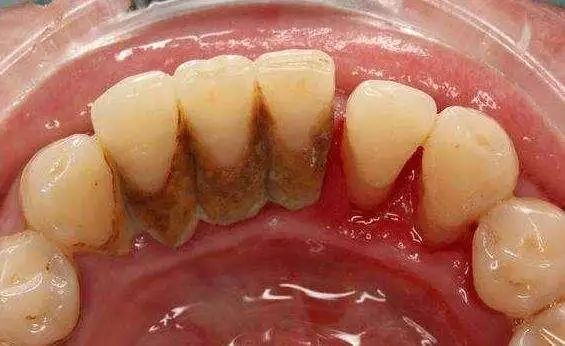

牙龈与牙根面之间不是紧密附着,而是存在一条0.5—2mm的浅沟,称龈沟。龈沟内易积存食物碎屑,附着菌斑,而且龈沟是难以彻底清洁的区域。

一般在刷牙之后的半小时内即会有新的菌斑形成,久而久之即成为牙结石,这些细菌会引起牙龈炎、牙周炎、出血、口臭,最终引起牙齿松动,甚至脱落。

而洗牙,是借由各种器械来去除这些附着于齿颈与牙龈沟之间的牙结石及牙菌斑,可以减轻牙龈炎、牙周炎的炎症状况。